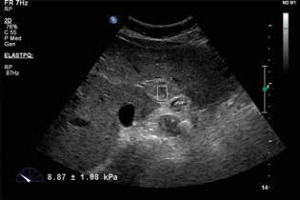

Throughout the entire examination the patients were allowed to hold their breath after it had been inspired as deeply as possible. The B-mode examination revealed the target lesion in the liver. The size and depth of the target lesion were determined. Lesions that were less than 2 cm and more than 8 cm in in depth were not included in the study. The SWE operation was performed with the same probe. In this method, called the elastoPQ technique, manual compression was not applied to the probe during the procedure. Measurements were obtained from a box that was approximately 0.5 × 1 cm wide on the screen. With this method, shear waves were sent to the tissue through a convex probe using a special pulse sequence technique, and the distribution rate of these waves in the tissue was measured. Measurements were given by the device in kPa and m/s. During the SWE, 2 measurements were taken from different points of liver masses and averaged, and 2 measurements were made from the liver parenchyma and averaged. SWE values taken from the liver parenchyma were in an area free of large vessels and more than 2 cm away from the liver lesion. The mass/parenchyma ratio was also evaluated. Moreover, according to the standard deviation value calculated automatically by the device in each measurement, those with a standard deviation value below 5 kPa were classified as homogeneous, and those above 5 kPa were classified as non-radially or radially heterogeneous. The radial character was established on the aspect of convergence towards the centre of the lesion, of the lines of maximum stiffness. An attempt was made to take the measurements from solid areas as often as possible. Cystic and calcific areas were not measured. All the measurements for each patient were obtained at the same depth. This depth was determined according to the central part of the mass, and the normal parenchymal measurement was obtained at the same depth.

Table 3 shows the masses and mean elasticity values. It can be seen that in the normal parenchymal area measurements, the mean elasticity values were 5.92 ± 3.99 kPa and 1.36 ± 0.53 m/s. The upper, lower, and average elasticity values of the masses are shown in Figures 1 and 2.